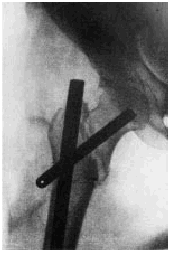

Tras su jubilación el Prof. Anschütz fue sustituido, hasta el año 1945, por el Prof. A. W. Fischer que, como su antecesor, apoyó las actividades clínicas y científicas de Küntscher, quien apoyado en ensayos mecánicos, en experimentos realizados en animales y en cadáveres y aprovechando su experiencia quirúrgica con los clavos trilaminares realizó, el 18 de noviembre de 1939, la primera intervención con un clavo intramedular en una fractura diafisaria proximal del fémur, en un paciente de 35 años (Fig. 4). Poco tiempo después, en marzo de 1940, en la reunión de la Asociación Alemana de Cirugía (Deutsche Gesellschaft für Chirurgie), en Berlín, presentó los resultados de 13 enclavados intramedulares en diferentes tipos de fracturas de los huesos largos (11 en fémures, uno en el húmero y otro en el cúbito) concluyendo, llevado por la ilusión y la certeza en las posibilidades de su método que la «técnica es adecuada para todas las fracturas transversales y oblicuas y puede indicarse en la mayoría de las fracturas diafisarias espiroideas. Además de en el tratamiento de fracturas, los clavos intramedulares están indicados en osteotomías, distracciones de callos, artrodesis y para el tratamiento de la pseudartrosis». No es de extrañar que con este ímpetu y temiendo que la indicación principal del tratamiento de las fracturas fuera quirúrgica, influyentes cirujanos alemanes como Nordmann, de Berlín, y König, de Würzburg, criticaron duramente a Küntscher y su método. Para comprender la situación, basta ver la vehemencia con la que König se preguntó en voz alta sobre la necesidad de golpear el hueso con un clavo tan horroroso una vez estaba reducida la fractura. Tan sólo su jefe, el Prof Fischer, le defendió en un encarnizado debate, señalando que «estoy convencido que la técnica de Gerhard Küntscher significa un gran progreso».

Figura 4. Primer enclavado intramedular realizado en un paciente.